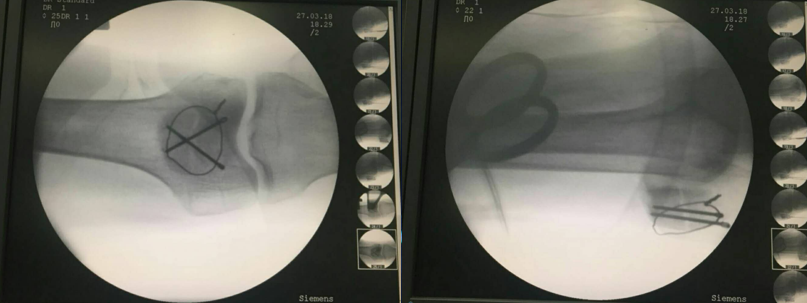

先扪及髌骨上下极及断端,用电钻于髌骨上极打一骨洞

利用腰穿针带过钢丝

再用利用腰穿针引导钢丝

收紧钢丝打结使其骨折端复位,透视发现复位欠佳

继续收紧钢丝,骨折复位,剪断钢丝

将钢丝埋于深处

由下方两钢丝口打入两髌骨

术后切口照片(无需缝合)

病房照(创口小,仅4个。最大的内下口约4MM)

术后复查